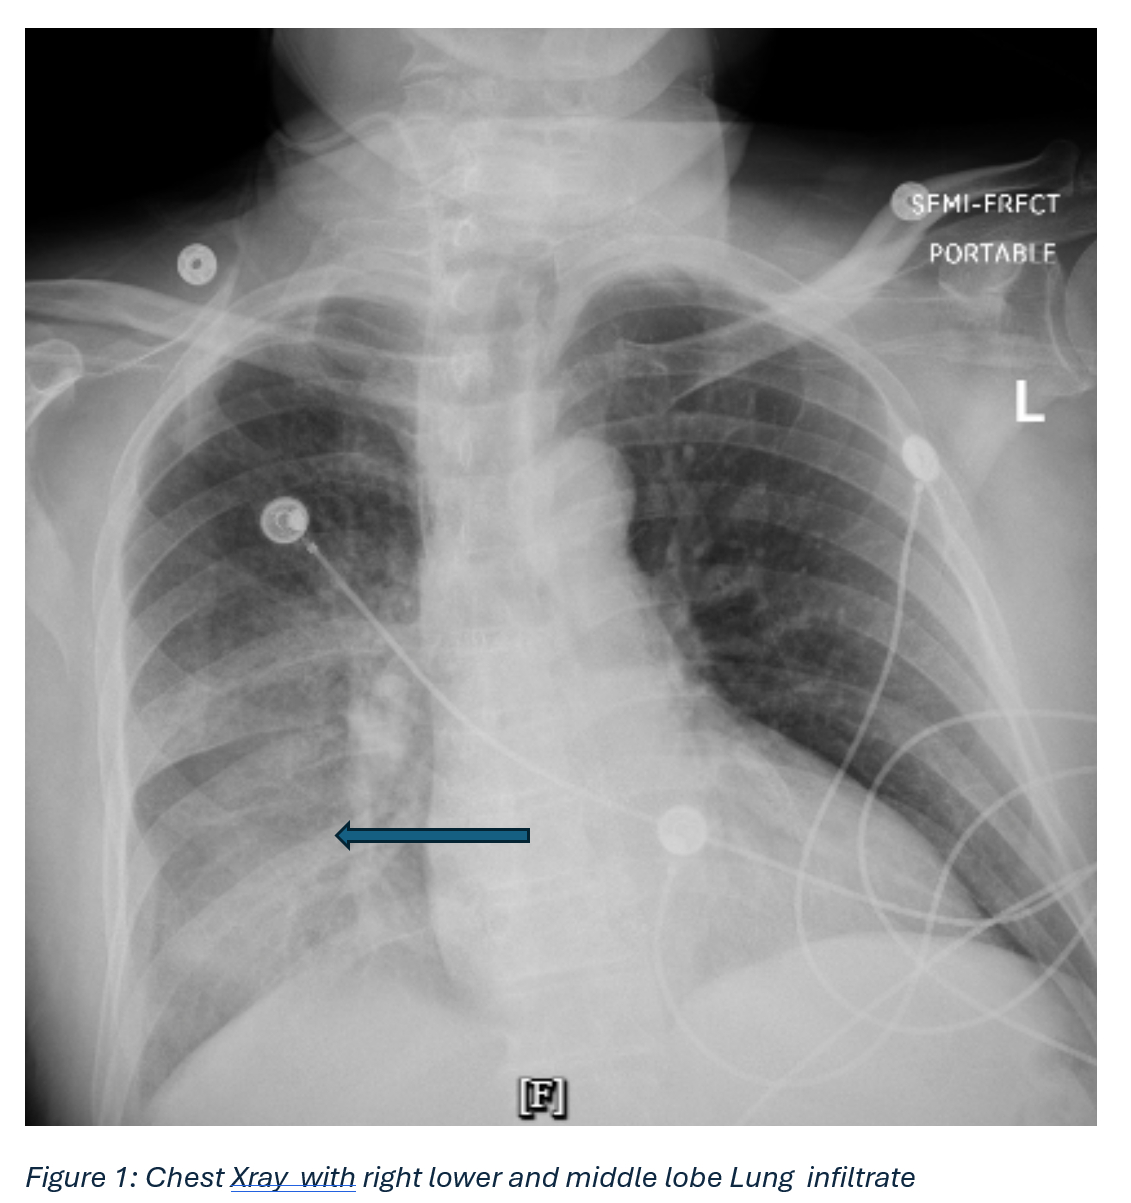

Description of the Case: A 62-year-old male was admitted with altered mental status, fever, hypotension, and respiratory distress. Initial workup revealed sepsis with severe hyponatremia (Na 114 mEq/L), acute kidney injury (Cr 1.54 mg/dL), elevated lactate (4.0 mmol/L), and rising troponin levels (195→483 ng/L). He developed transient atrial flutter that resolved spontaneously. Chest imaging showed right lower lobe infiltrates, and urine antigen testing confirmed Legionella pneumophila.